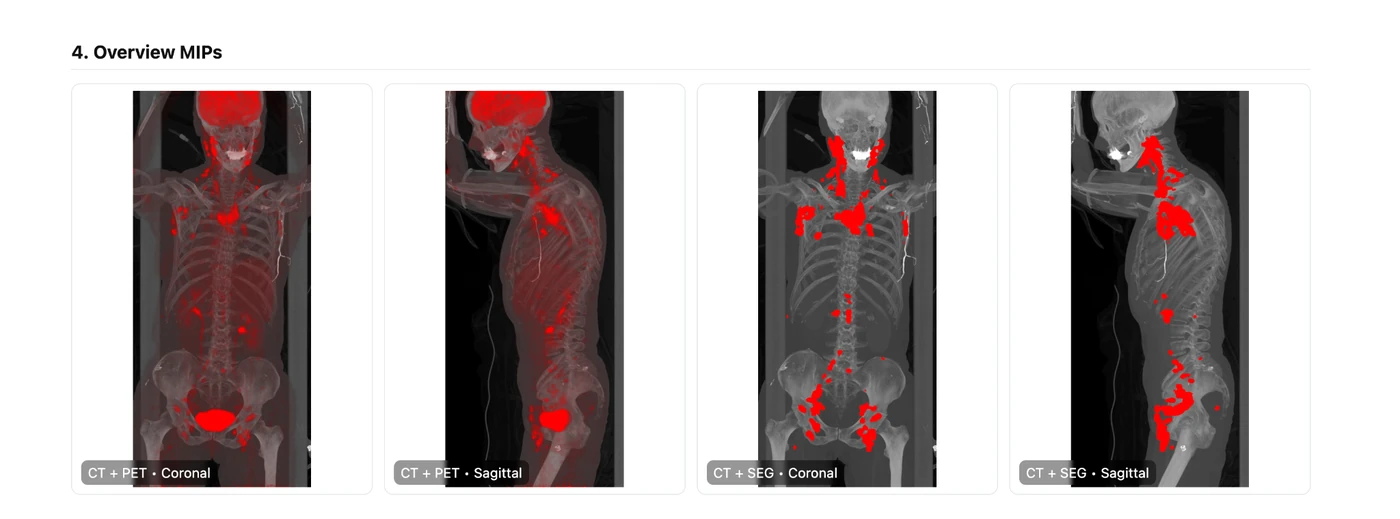

Overview MIP images from the sample PET/CT report

Overview MIPsThe left two images are straight from the unmodified PET/CT. The right two show the modeled tumor mask, allowing a physician to perform instant visual QC of what the software marked as disease.